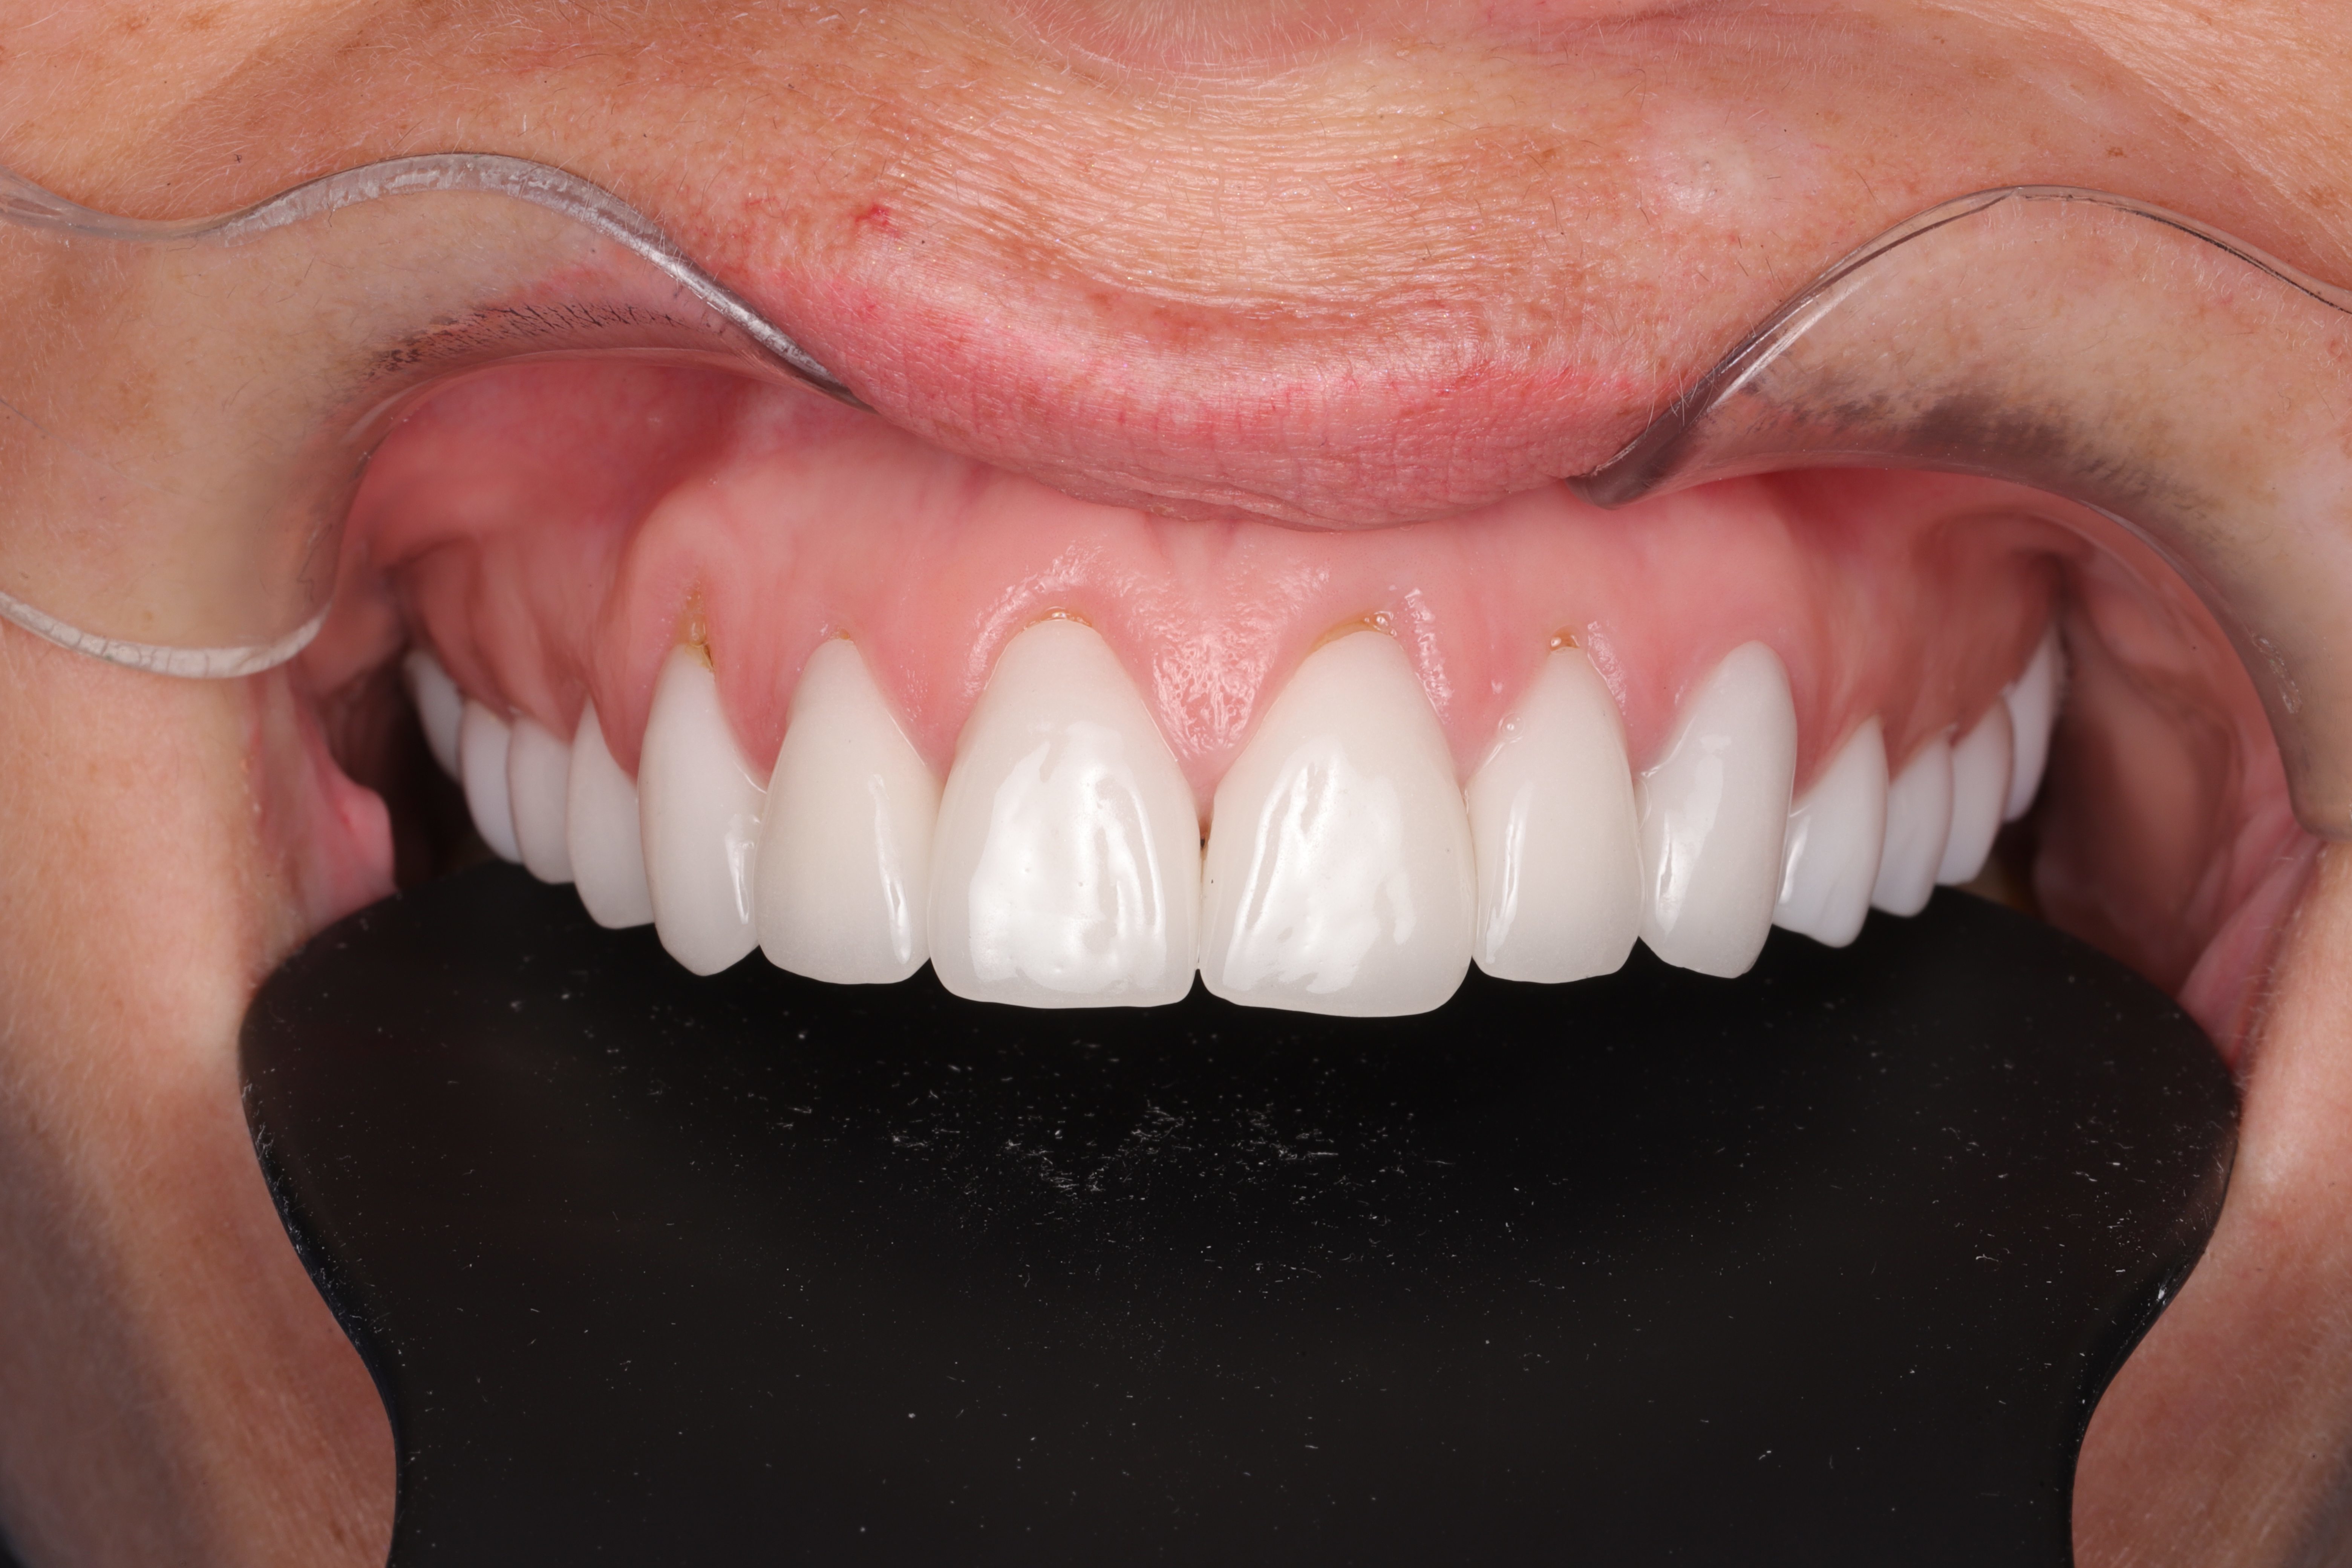

• Complete coverage of the exposed root and restoration of a harmonious gum line.

• Reduction of tooth sensitivity and prevention of root caries.

• Thickening and strengthening of the gingival margin for long-term stability.

• Noticeable improvement in smile aesthetics, especially in the anterior region.